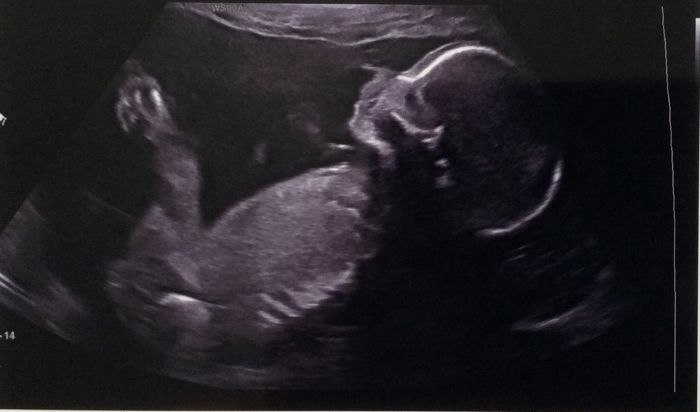

Ahoj holkyyyyyyy :-))) jsem doma. UTZ byl náročný- na zádech fakt nemůžu dýchat, ale krásnýýýýý. Malý je v pořádku a doktor dokonce řekl, že minule jsme měli minimální riziko vad a teď si tu jistotu prý můžeme znásobit 7,7x. No super:-D Má 23 cm a 351 gr. Jediné, co není hezké, že mám doporučen sex.klid, páč placenta je přes branku. Když jsem se zeptala, zda se ještě vytáhne, netvářil se. Ale já ji vytáhnu. Kdybych začala špinit, musím hned do nemocnice a nesmím nic tahat. Jinak synek mě fakt rozesmál. Potřeboval na wc. Najednou se vrátil bez vyčůrání. Ptám se proč. " na dveřích je napsáno, že ve 13tt musí být plný močový měchýř" no, smála jsem se jak protržená:-))

[905816] juu krasna fotka !! Gratuluju uz se taky tesim na patek

[905816] juuu ten je krasnyy takova nadherna cunicka